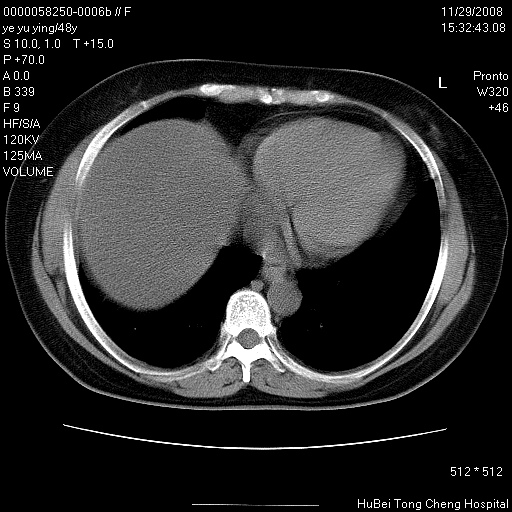

以下是引用zsl6918在2008-11-29 21:47:00的发言:[br]恶性肿瘤病史,转移瘤首先考虑。脂肪肝,胆囊结石。

以下是引用huenhao在2008-11-29 22:11:00的发言:[br]脂肪肝,胆囊结石。左肺病灶建议定期复查。

以下是引用liuyue在2008-11-30 5:44:00的发言:[br]1.左肺病变,首先考虑感染性病变,转移待排;建议治疗后复查。[br]2.肝脏密度普遍减低,考虑与化疗有关。[br]3.胆囊结石.